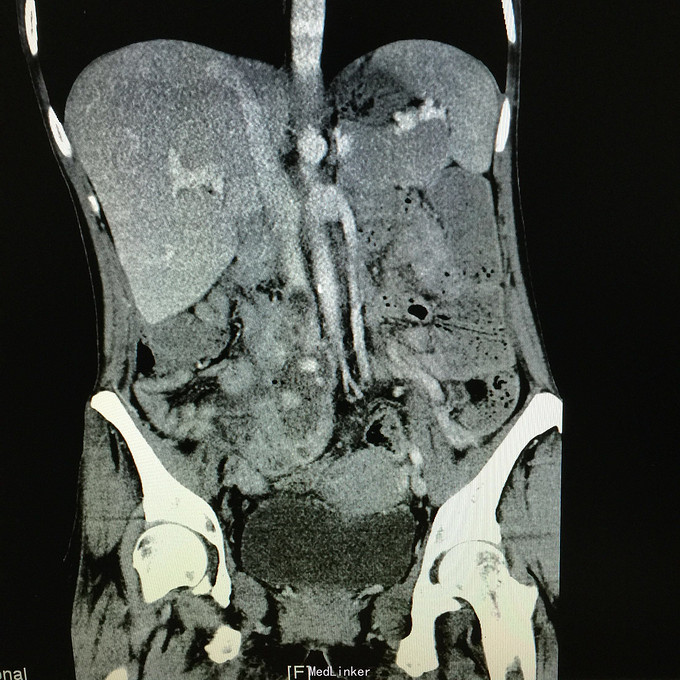

查体无特殊。 辅助检查:中下腹CT平扫+增强+CTU+CTA示:1.右输尿管中上段病变,考虑恶性病变,周围多发淋巴结转移,髂总动脉及髂外动脉起始部、髂内动脉中上段受侵闭塞,右侧腰大肌可疑受侵;建议输尿管镜检查;右肾重度积水,右肾功能明显受损。2.CTA示:右肾动脉纤细,肝右动脉起源于肠系膜上动脉。3.子宫体密度不均匀,建议MRI检查。中下腹MRI平扫+增强+MRU检查结果类似。

患者术后2月出现反复臀部疼痛,左侧为主,疼痛跑迷宫为隐痛,于翻身及活动时加重,卧床休息可稍缓解,多于下午出现,伴有发热,最高达39℃,在当地医院予“氟康唑”及止痛治疗后稍有缓解,但仍反复发热。后疼痛加剧,并出现双下肢疼痛,以大腿外侧为主,无间歇性跛行,无小腿及双足麻木疼痛不适,行对症治疗后效果不佳,于2015-10-9再次返院,予消炎止痛、营养支持及营养神经等治疗。查CT及MRI均提示骶髂关节炎症及腹膜后巨大病变,右侧髂总动脉及髂内、外动脉上段、右侧腰大肌受累。2015-10-15 14:00患者出现右下肢剧烈疼痛、右下肢乏力和麻木,随后出现2次血便,每次量约100ml,暗红色,无腹胀、腹痛等不适,查血提示白细胞 28.17*10E9/L,中性粒绝对值 25.33*10E9/L,血红蛋白56g/L,予止血、输血、抗真菌、止痛等治疗。19:00再次出现右下肢剧烈疼痛伴右下腹痛,查体:BP 80-90/50-60mmHg,P 100-106次/分,R 23次/分,SpO2 100%。右下腹轻压痛,反跳痛阴性,右下肢蹲背伸及踝背伸肌力II-III级,立即行全腹CT检查,示右髂总动脉假性动脉瘤破裂,予加强输注浓缩红细胞及补液支持治疗。清介入科会诊,考虑脓肿和感染为介入血管腔内支架置入治疗的禁忌症,建议予血管外科行开放手术,予患者及家属沟通,并转外院血管外科进一步治疗。